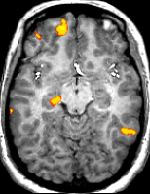

Dr. Goodale and his colleague at the time, Dr. David Milner, postulated that there were two ways of storing information about an object’s shape: one for perception, the other for action. He and other researchers continue to explore this topic today, equipped with modern scientific technology. Dr. Goodale does many functional MRI studies, trying to see which areas of the brain are most active during certain tasks.